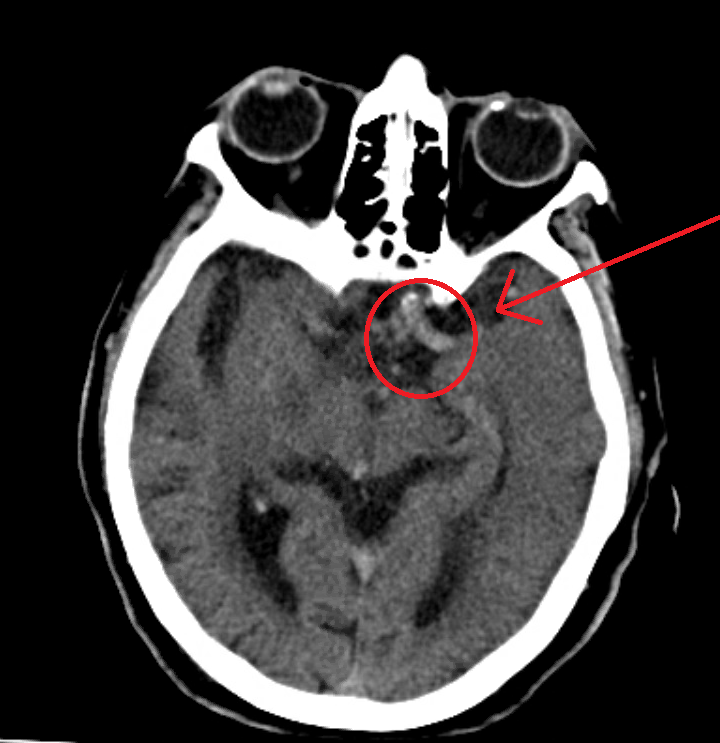

Case report: We had a patient come in for a chief complaint of sudden onset right sided weakness, on eliquis for atrial fibrillation, found altered at home, hypertensive in the systolic 200’s en route. We were suspecting a massive head bleed; instead, the CT non contrast revealed this classic sign of hyperdense MCA. Patient was prepped for an emergent thrombectomy.

The ‘hyperdense MCA sign’ refers to an appearance of increased attenuation of the proximal middle cerebral artery (MCA) that is often associated with thrombosis of the M1 MCA segment and may be the only diagnostic feature on computed tomography early after ischaemic stroke. It is seen within 90 minutes after the event. | https://pubmed.ncbi.nlm.nih.gov/11070370/